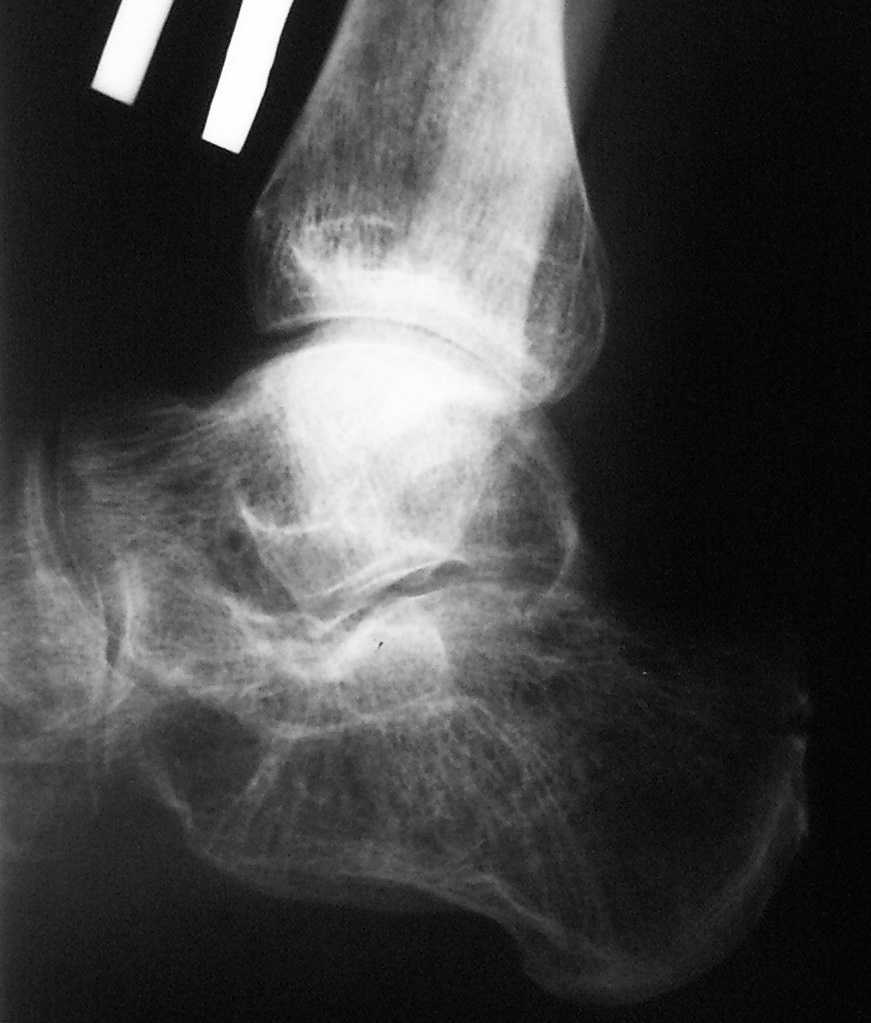

После перелома (вколоченный) пяточной кости без смещения развился артроз в таранно-пяточном суставе (посттравматический артроз). Хожу более менее нормально (то есть хромота не всегда, но присутствует). В зависимости от нагрузки если «перехожу» то есть достаточно много стою или хожу в течение дня, то к вечеру появляется боль. Разогнуть стопу больно, и также присутствует «стартовая» боль. Как правило, за ночь боль проходит. Сильного дискомфорта я не испытываю (так как стараюсь контролировать нагрузку), только когда перехожу (из-за работы), и в этот момент желание сделать операцию доминирует. Дистрофии икры нету. Перелом был год назад. Думаю пойти на артродез. Но боюсь оперативного вмешательства. То есть хочу узнать. Есть ли смысл в моей ситуации делать операцию или отложить "до последнего". И полечиться консервативно или это только убирает симптомы и рано или поздно операцию придётся сделать. Снимок выкладываю последний сделан 03.07.2010 если необходим актуальный снимок, напишите, сделаю, размещу.